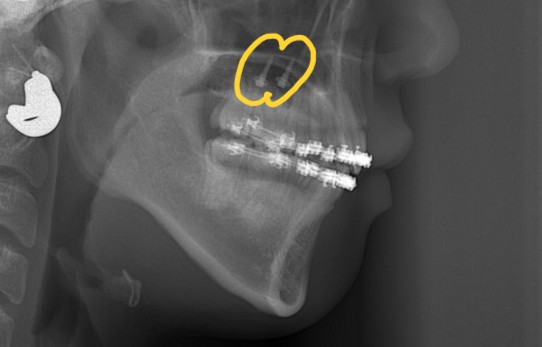

レントゲン写真で確認すると、

この患者さんの場合、

【診断】

#1.上下顎前突

(噛み合わせは上顎前突傾向)

#2.歯と顎の不調和による(軽度の)叢生

と診断しました。

矯正後の状態をレントゲン写真で確認すると、